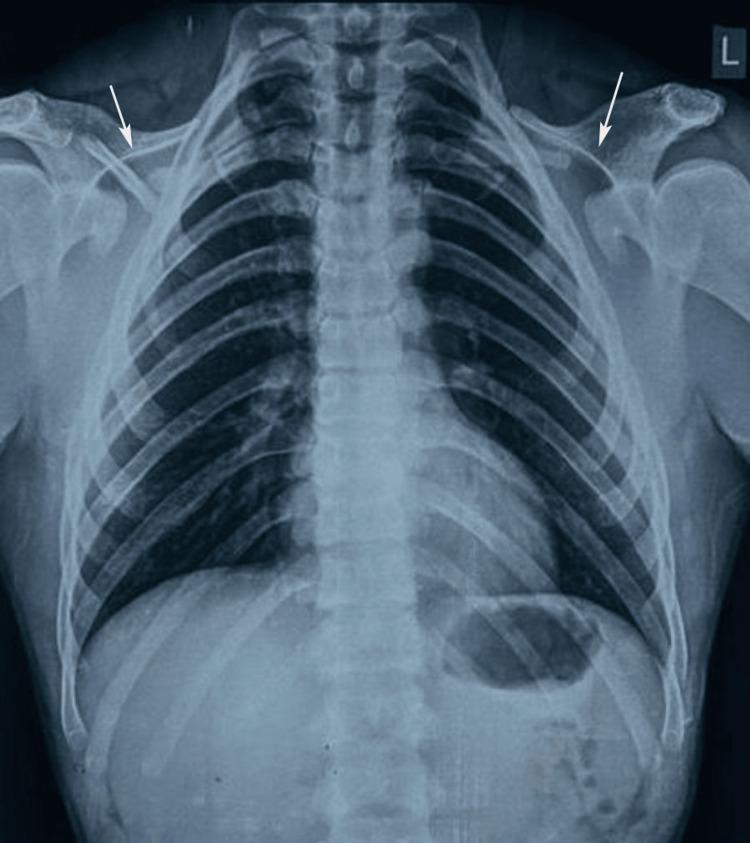

This report describes an unusual case of a 27-year-old male presenting with cleidocranial dysplasia (CCD), a rare genetic disorder affecting bone and dental development. The patient exhibited classic features, including short stature, drooping shoulders with hypermobility, broad forehead, maxillary deficiency, and mandibular prognathism. Intraoral examination revealed multiple missing teeth, retained deciduous teeth, and gingival swelling in the maxillary anterior region. Radiographic evaluation, including orthopantomogram and cone beam CT (CBCT), revealed 45 impacted permanent and supernumerary teeth, a rare finding, along with multiple dentigerous cysts, notably a large cyst in the right maxilla causing cortical plate breaches and nasal cavity displacement. Additional skeletal abnormalities included hypoplastic clavicles, open cranial sutures, and underdeveloped sinuses. Genetic testing confirmed a Runt-related transcription factor 2 ( gene) mutation, thus confirming the diagnosis. The extensive number of impacted teeth and cystic lesions sets this case apart from the typical presentations, which usually involve fewer supernumerary teeth and rare cystic changes. The complexity of dental and skeletal anomalies necessitates a multidisciplinary approach involving oral surgery, orthodontics, and prosthodontics to restore function and aesthetics. Early diagnosis through clinical, radiographic, and genetic assessments is crucial to prevent complications, such as cyst expansion or bone resorption. This case emphasizes the importance of comprehensive evaluation and tailored treatment planning in managing the severe manifestations of CCD, highlighting its diverse clinical spectrum and the need for individualized care.

本报告描述了一例不同寻常的病例,一名27岁男性患有锁骨颅骨发育不全(CCD),这是一种影响骨骼和牙齿发育的罕见遗传疾病。该患者表现出典型特征,包括身材矮小、肩部下垂且活动过度、额头宽阔、上颌骨发育不全以及下颌前突。口腔内检查发现多颗牙齿缺失、乳牙滞留以及上颌前部牙龈肿胀。影像学评估,包括全景曲面断层片和锥形束CT(CBCT),显示有45颗埋伏恒牙和多生牙,这一罕见发现还伴有多个含牙囊肿,尤其是右上颌的一个大囊肿导致皮质骨板破裂和鼻腔移位。其他骨骼异常包括锁骨发育不全、颅骨缝未闭合以及鼻窦发育不全。基因检测证实存在一种与Runt相关的转录因子2(基因)突变,从而确诊。大量的埋伏牙和囊性病变使该病例有别于典型表现,典型表现通常涉及较少的多生牙和罕见的囊性改变。牙齿和骨骼异常的复杂性需要口腔外科、正畸科和修复科等多学科方法来恢复功能和美观。通过临床、影像学和基因评估进行早期诊断对于预防并发症(如囊肿扩大或骨质吸收)至关重要。该病例强调了在管理CCD严重表现时进行全面评估和制定个性化治疗计划的重要性,突出了其多样的临床谱以及个性化护理的必要性。